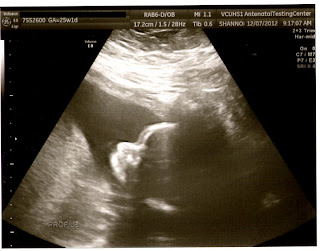

We had our ultrasound today to get the rest of the measurements we needed from our anatomy scan and everything looks great. The tech managed to get this profile shot for me and I don't know but from what I can see it looks like Lorelai will have her dad's nose. :D I'm just hoping that she won't have his terrible nosebleeds.